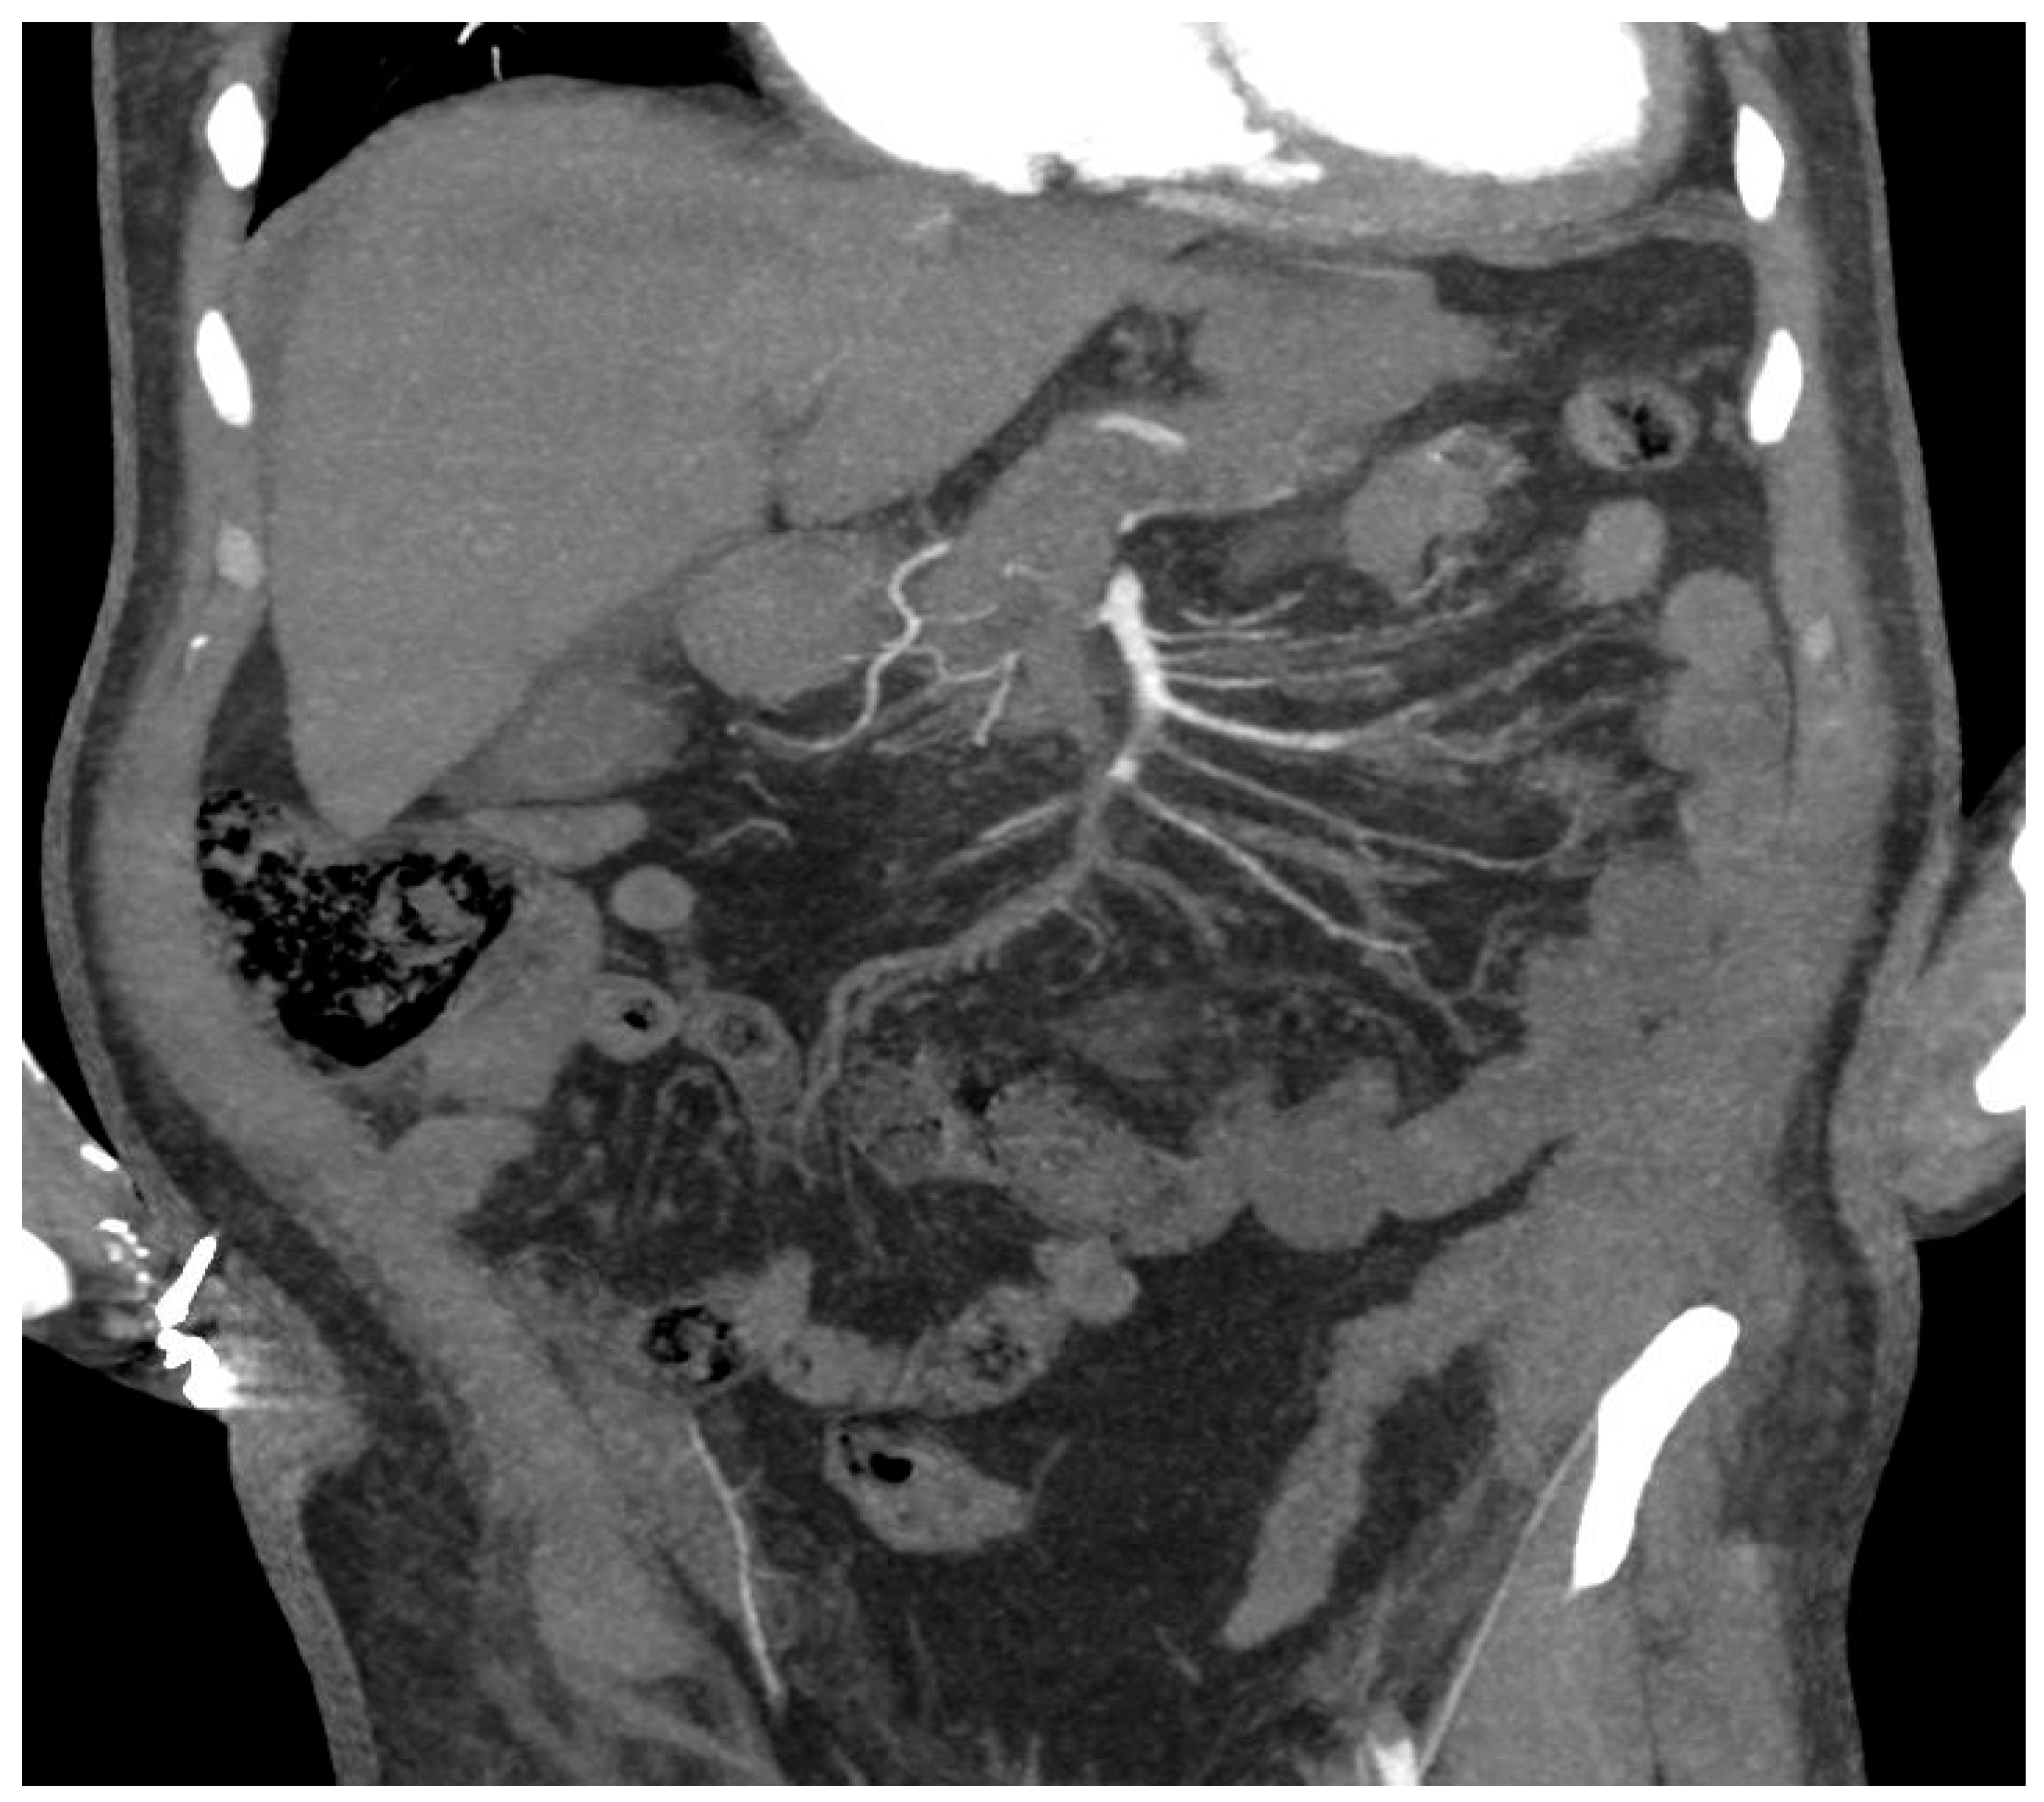

- Focal ischemia of the splenic parenchyma in two patients (18.2%) (Figure 4);